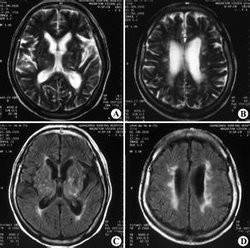

【华夏原创】可逆性后部白质脑病综合征

图片尺寸1280x720